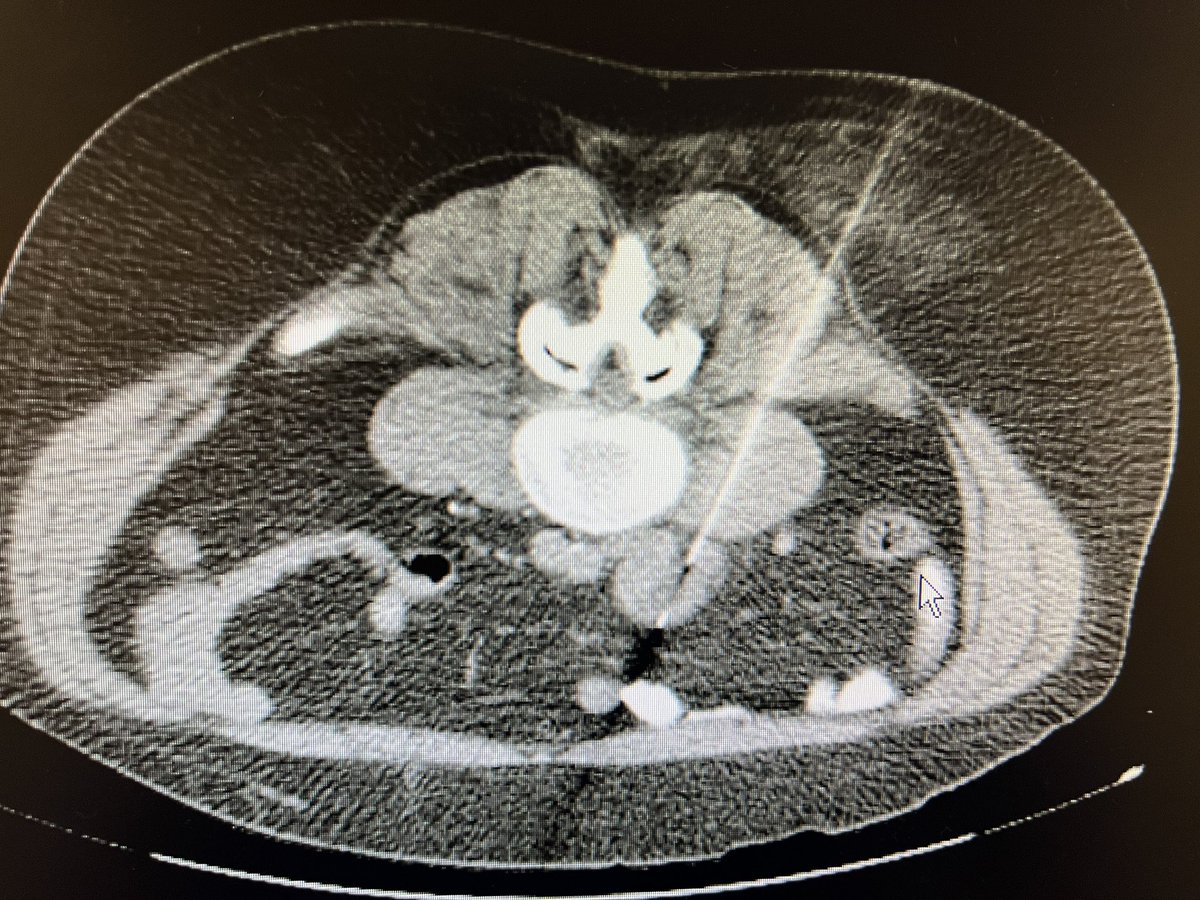

When you biopsy iliac node , not only care about IVC or aorta but also think of ureter. Ureter the “recurrent laryngeal nerve of abdomen” #radres #radtwitter #futureradres #FOAMrad #radiology #AbdRad #irrad

When you biopsy iliac node , not only care about IVC or aorta but also think of ureter. Ureter the “recurrent laryngeal nerve of abdomen”

#radres #radtwitter #futureradres #FOAMrad #radiology #AbdRad #irrad